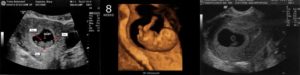

Несмотря на то, что ваш кроха еще очень маленький, он уже похож на человечка: при УЗИ на этом сроке уже можно отчетливо различить его головку и туловище, размеры которых сейчас почти одинаковые, ручки и ножки, глазки, начинающие развиваться ушки.

Также вам будет дано направление на УЗИ, которое нужно будет сделать на сроке 11–14 недель. Это первое скрининговое ультразвуковое исследование, коорое позволяет исключить хромосомную патологию, пороки развития плода, а также точно установить гестационный возраст плода.

Можно ли сделать УЗИ на 8 неделе беременности?

Ультразвуковое исследование на таком сроке проводится по показаниям со стороны матери или плода.

На таком сроке сложно оценить развитие ребенка, ведь он еще слишком маленький, не сформированы все органы и системы. Оптимальный срок для первого УЗИ — 11–13 недель.

На этом сроке малыш уже достаточно развит, и можно измерить все необходимые параметры, исключить хромосомную патологию, аномалии развития.